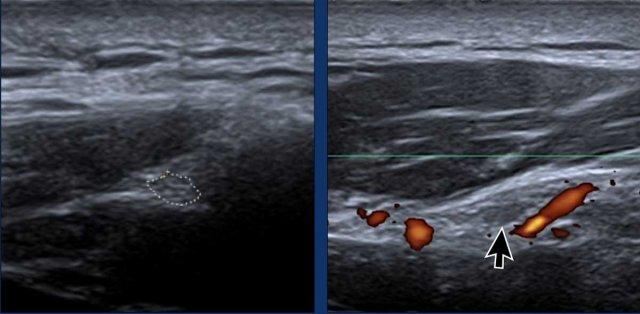

Thần kinh trên vai xuất hiện dưới dạng cấu trúc hình ống giảm âm với hình thái bó sợi (mũi tên).

Doppler năng lượng có thể hữu ích để theo dõi các mạch máu trên vai nhằm xác định vị trí thần kinh.

Kiểm tra các nang hạch, có thể xuất hiện dưới dạng các cấu trúc giảm âm, chứa dịch, chèn ép thần kinh trên vai.

Các nang này thường liên quan đến rách sụn viền ổ chảo mặt sau trên.